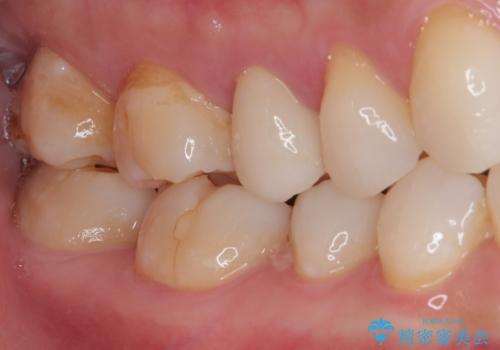

- むし歯と銀歯を気にして来院された患者様です。

銀歯の歯は既に根管治療がされており、根尖部に病変が認められないため、根管治療を行うことなくオールセラミッククラウンにて補綴治療を行うこととしました。

むし歯の症状のある歯は、ややしみることがある程度でしたが、レントゲン写真では非常にむし歯が大きく、神経組織に迫っている状態でした。

術前診査では神経を全て取る可能性は低いと予想されましたが、一部切除する可能性があることを伝えた上で治療を行うこととしました。

やはりむし歯は大きく、一部歯髄を切除することとなりましたが、その後は良好な経過をたどっています。